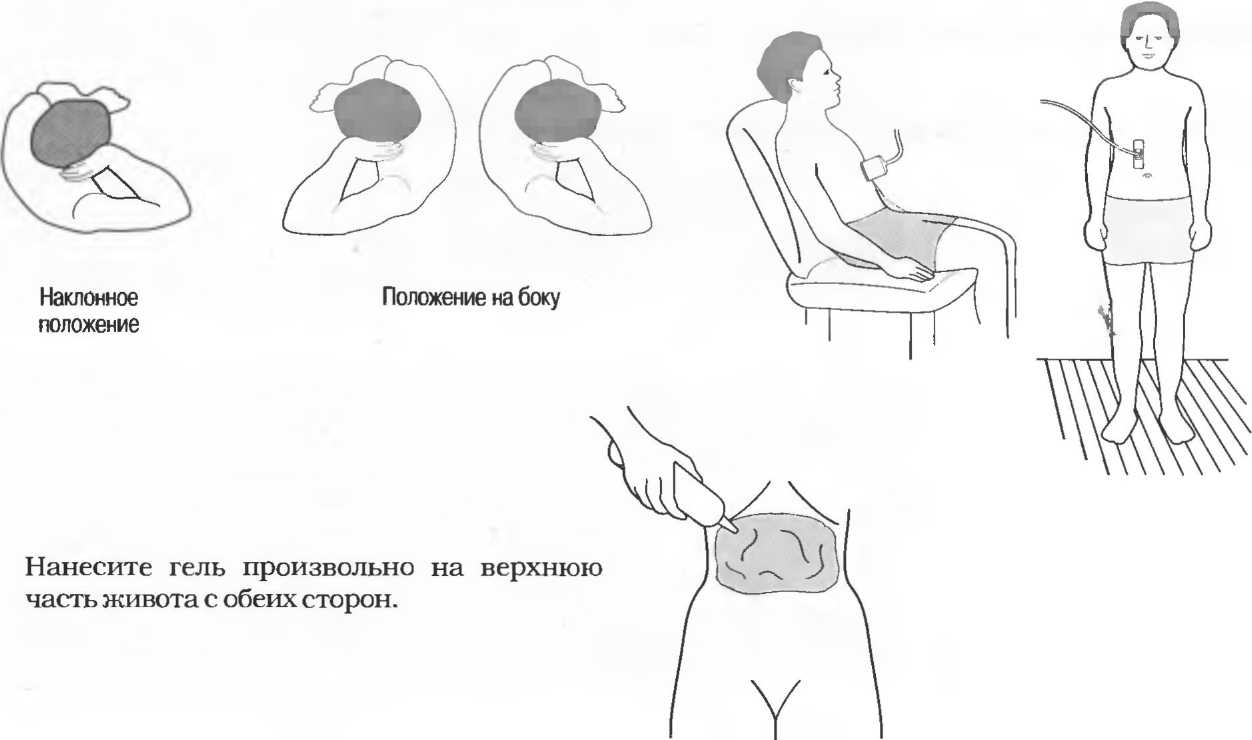

1. Подготовка

Пациент не должен пить и есть в течение 8 ч перед исследованием. Если жидкость необходима для предотвращения дегидратации, можно давать пациенту только воду. При острой симптоматике исследование можно проводить без подготовки. Детям, если позволяют клинические условия, пища и вода не даются в течение 3 ч до исследования.